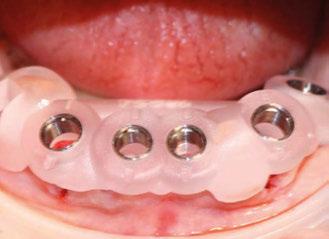

Presentamos el tratamiento rehabilitador de una paciente, realizado íntegramente en una sesión. Para este caso se ha utilizado un protocolo quirúrgico digital y guiado mediante la Plataforma de Planificación Bego Guide. Asimismo, se ha diseñado digitalmente una prótesis de carga inmediata atornillada e impresa con resina Bego VarseoSmile TriniQ®. Por lo tanto, se trata de un caso cuyo tratamiento precisa diferentes fases, pero efectuadas, todas ellas, el mismo día. De forma sencilla y cómoda para la paciente y el odontólogo, se ha obtenido una rehabilitación fija, funcional y estética. Palabras clave: Cirugía guiada, implantología oral guiada, cirugía sin colgajo, férula quirúrgica, rehabilitación fija maxilar, impresión digital, escáner intraoral, implantes dentales.

(Figuras 22 y 23). Se realiza fresado transgingival mínimamente invasivo y guiado hasta la inserción de los implantes, siguiendo el protocolo preestablecido e indicado (Figuras 24 a 26).

Dentro de la fase quirúrgica propiamente dicha, una vez terminada la inserción de los implantes y

comprobada su estabilidad primaria, colocamos pilares transepiteliales

Multiplus para registrar una impresión digital mediante escaneado sobre ellos (Figuras 27 a 29)

Ejecución técnica protésica

Dado que la estabilidad primaria se ha conseguido en la mayoría de los implantes, coincidiendo con la previsión propuesta en la planificación, procedemos ahora a la fase protésica. En el caso que nos ocupa, la paciente reside lejos, por lo tanto, colocamos tapones sobre los pilares transepiteliales y descansa en la sala de recuperación (Figura 30).

aproximadamente una hora y media. Usamos resina Bego VarseoSmile TriniQ® para puentes definitivos. Aunque en este caso la vamos a usar para confeccionar unas prótesis fijas atornilladas provisionales de larga duración, dado al aumento de dimensión vertical que vamos a realizar a la paciente, de esta forma obtendremos una neuroprogramación de la ATM reinstaurando una Dimensión Vertical apropiada y mejorando la estética facial de la paciente. Excluimos de la carga aquellos implantes que no obtuvieron una estabilidad primaria superior a 35 N/ cm2. El material permite la realización de una carga inmediata en material definitivo en puentes (Figuras 31 a 38).